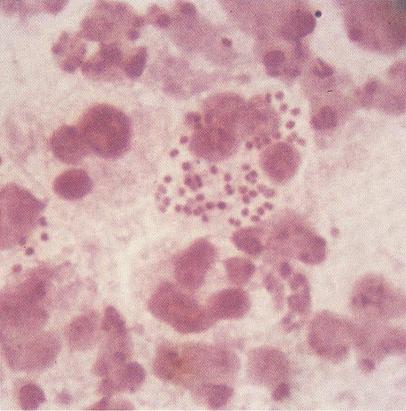

Fig. 21.5.5.4 Levuri prezente in secretia vaginala (coloratie Gram, x1000, imagine din colectia proprie a laboratorului)